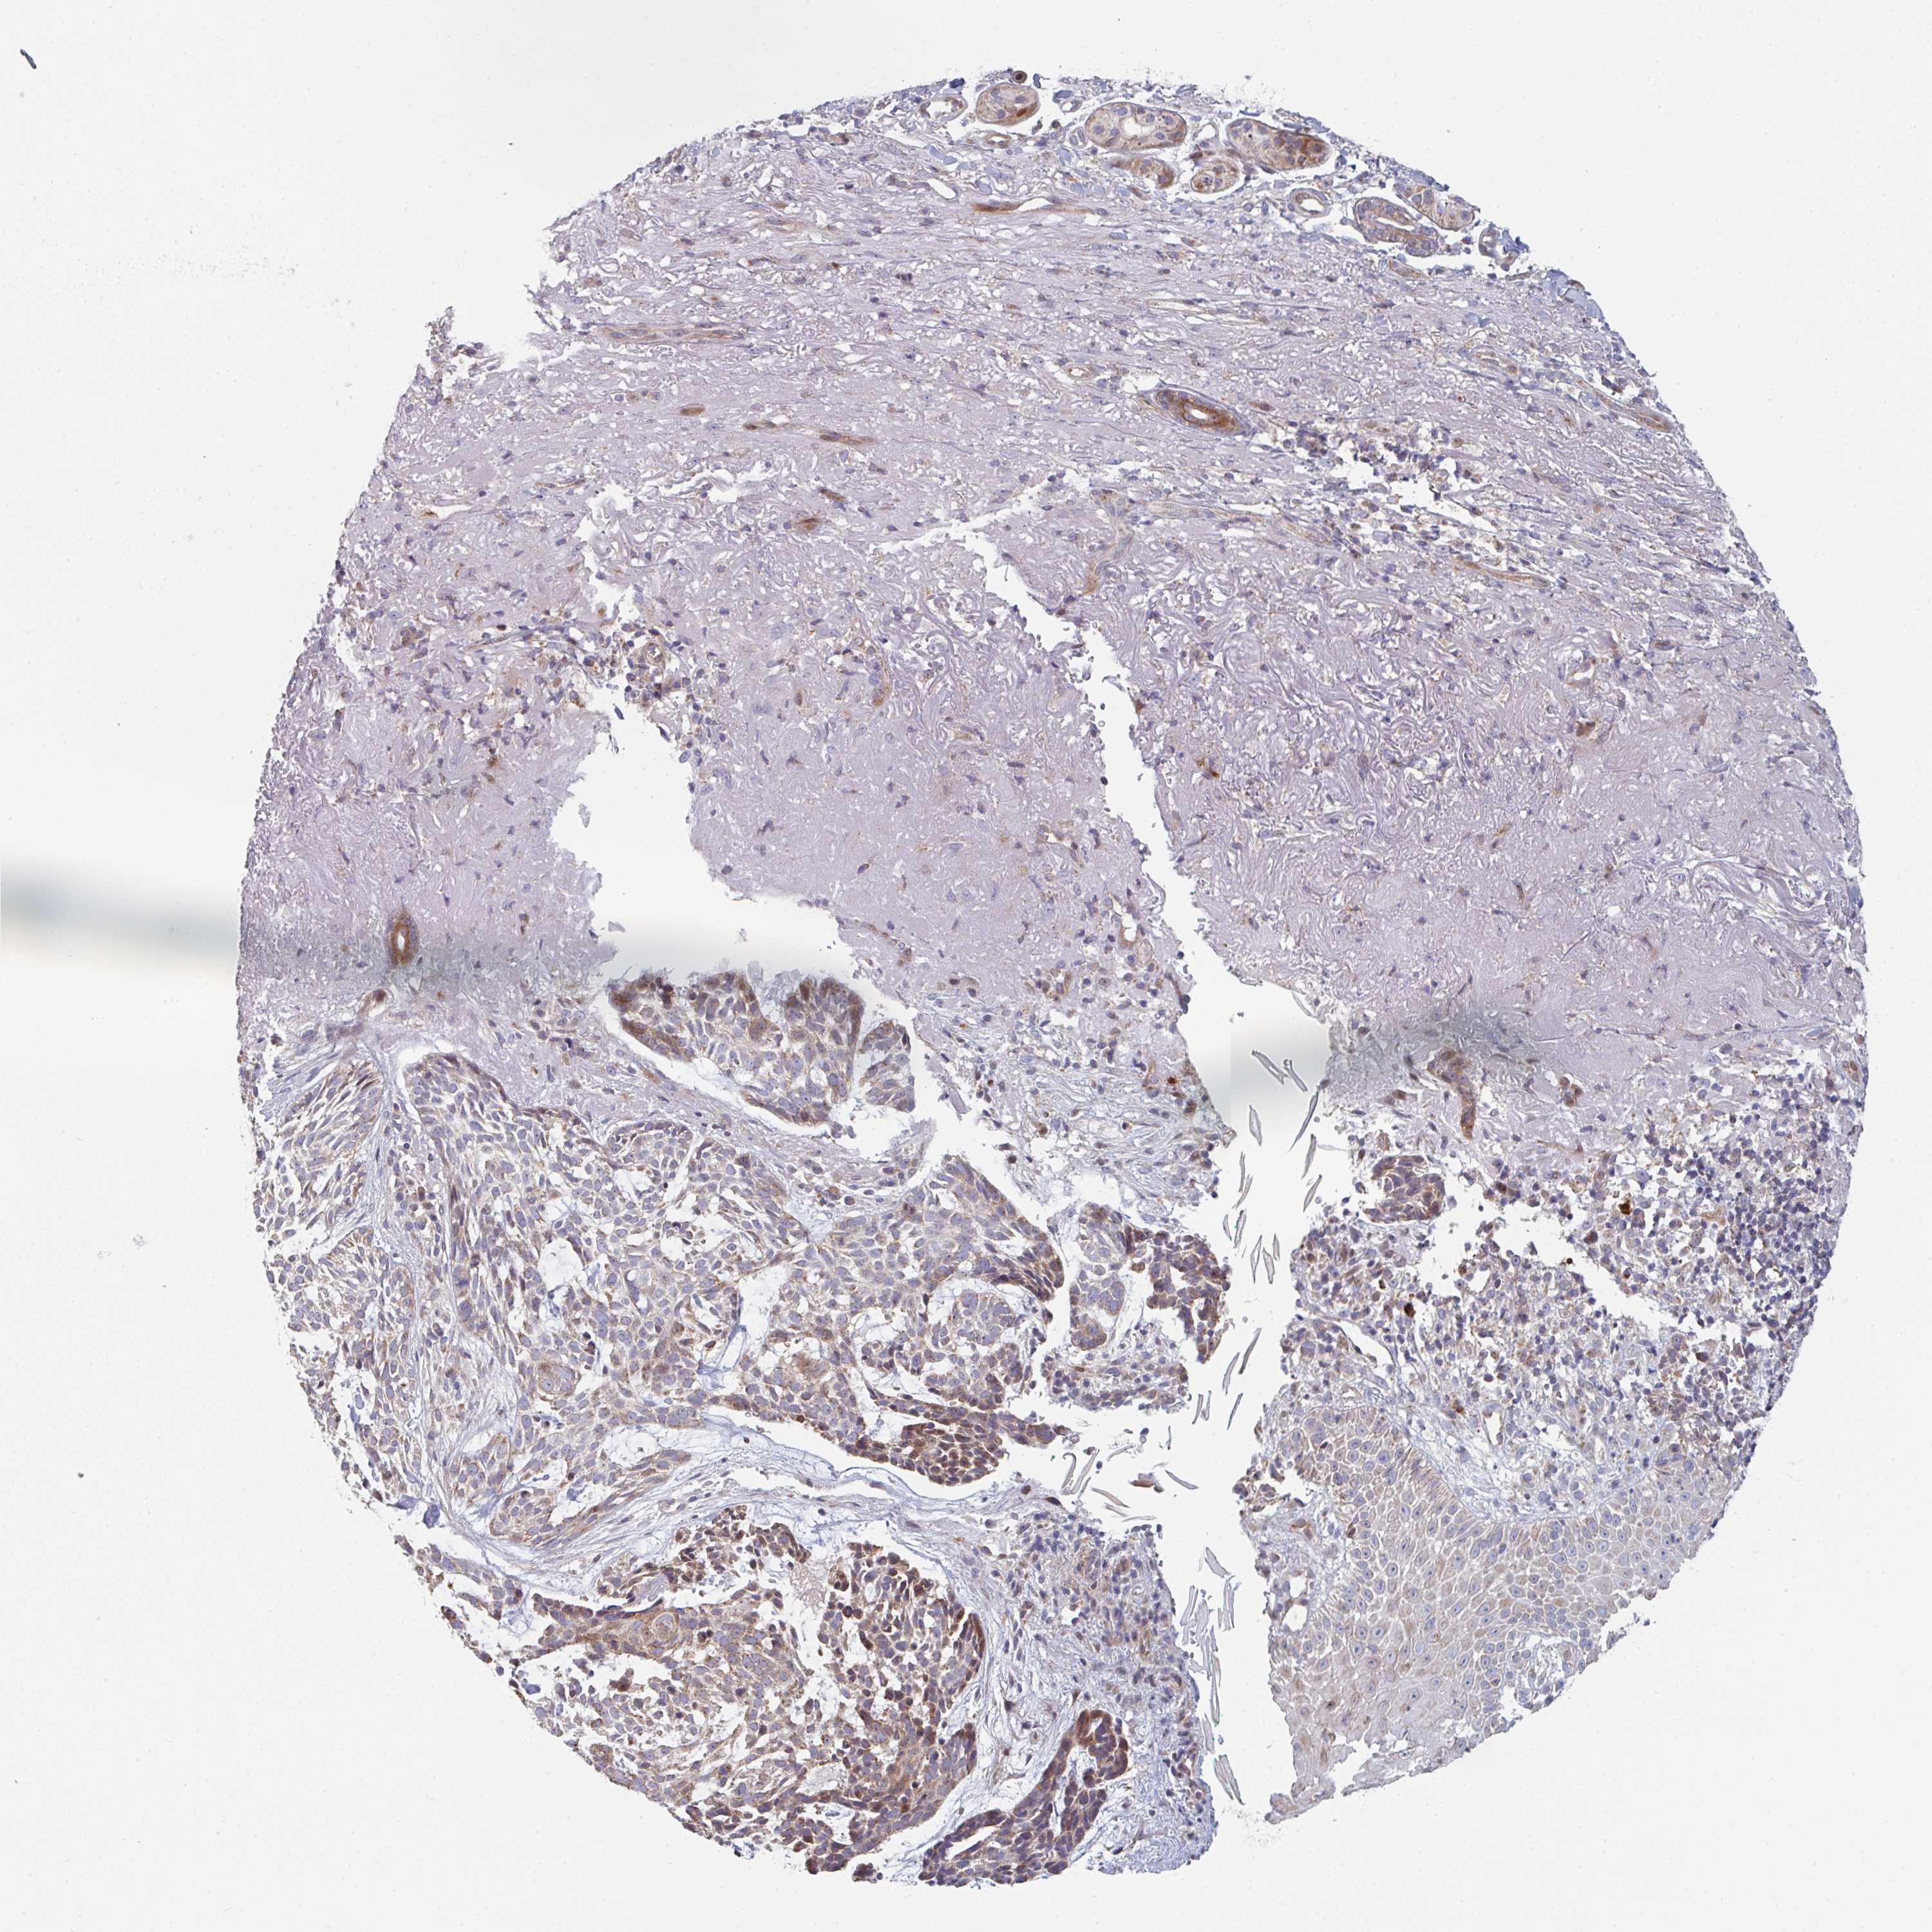

SKIN CANCER - Protein expressioni

A mouse-over function shows sample information and annotation data. Click on an image to view it in a full screen mode. Samples can be filtered based on level of antibody staining by selecting one or several of the following categories: high, medium, low and not detected. The assay and annotation is described here.

Antibody stainingi

Antibody staining in the annotated cell types in the current human tissue is reported as not detected, low, medium, or high, based on conventional immunohistochemistry profiling in selected tissues. This score is based on the combination of the staining intensity and fraction of stained cells.

Each image is clickable and will lead to virtual microscopy that enables deeper exploration of all samples and also displays staining intensity scores, fraction scores and subcellular localization as well as patient and tissue information for each sample.

Antibody HPA057795

Staining

High

Medium

Low

Not detected

Intensity

Strong

Moderate

Weak

Negative

Quantity

>75%

75%-25%

<25%

None

Location

Nuclear

Cytoplasmic/membranous

Cytoplasmic/membranous,nuclear

Basal cell carcinoma

Squamous cell carcinoma, NOS